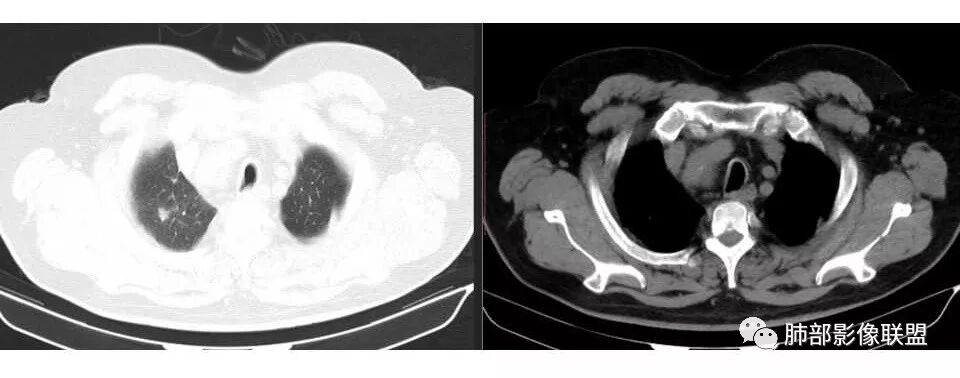

市医院--时建文: 右肺门占位性病变伴纵隔淋巴结肿大,鳞癌?小细胞癌?淋巴瘤待除外,右肺上叶结核。

甄德强:小病灶大转移,小细胞肺癌。

小溪流: 老年男性,有吸烟史,右肺门及纵隔肿物,考虑鳞癌伴纵隔淋巴结转移,右肺上叶阻塞性炎症。

wkj: 40岁以上吸烟男,右肺上叶新生物,纵隔新生物大于肺新生物,纵隔呈融合,冰冻,气管外压,血管疑似未受累,仅包绕,考虑小细胞。

张帅: 患者以肢体无力就诊,既往有吸烟史,胸CT:右肺门占位性病变,密度不均,病灶内病灶内支气管明显狭窄,走行僵硬,病灶边缘光滑,呈浅分叶,未见明显毛刺,对中叶支气管明显挤压。右肺内可见散在片状实变影,前纵隔淋巴结明显肿大,内可见低密度区,2r 4r 7 10r淋巴结明显肿大。诊断考虑恶性方向,肺癌(小细胞)并纵隔肺门淋巴结转移?淋巴瘤?

1.右肺上叶不规则结节影,右肺门及纵隔多结节并形成巨大块影,密度均匀,沿途支气管明显狭窄。

原发灶小或隐匿,肺门纵隔淋巴结异常增大,所谓“娘小崽大”常见于肺小细胞癌!